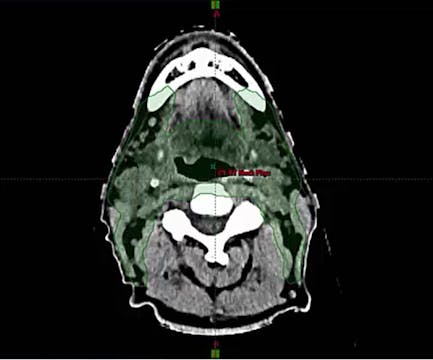

08/10/2021 - Dr. Kenneth Hu - Radiation Oncology - US Head & Neck

Chartrounds US - Head and Neck Cancer

Base of Tongue, Unknown primary